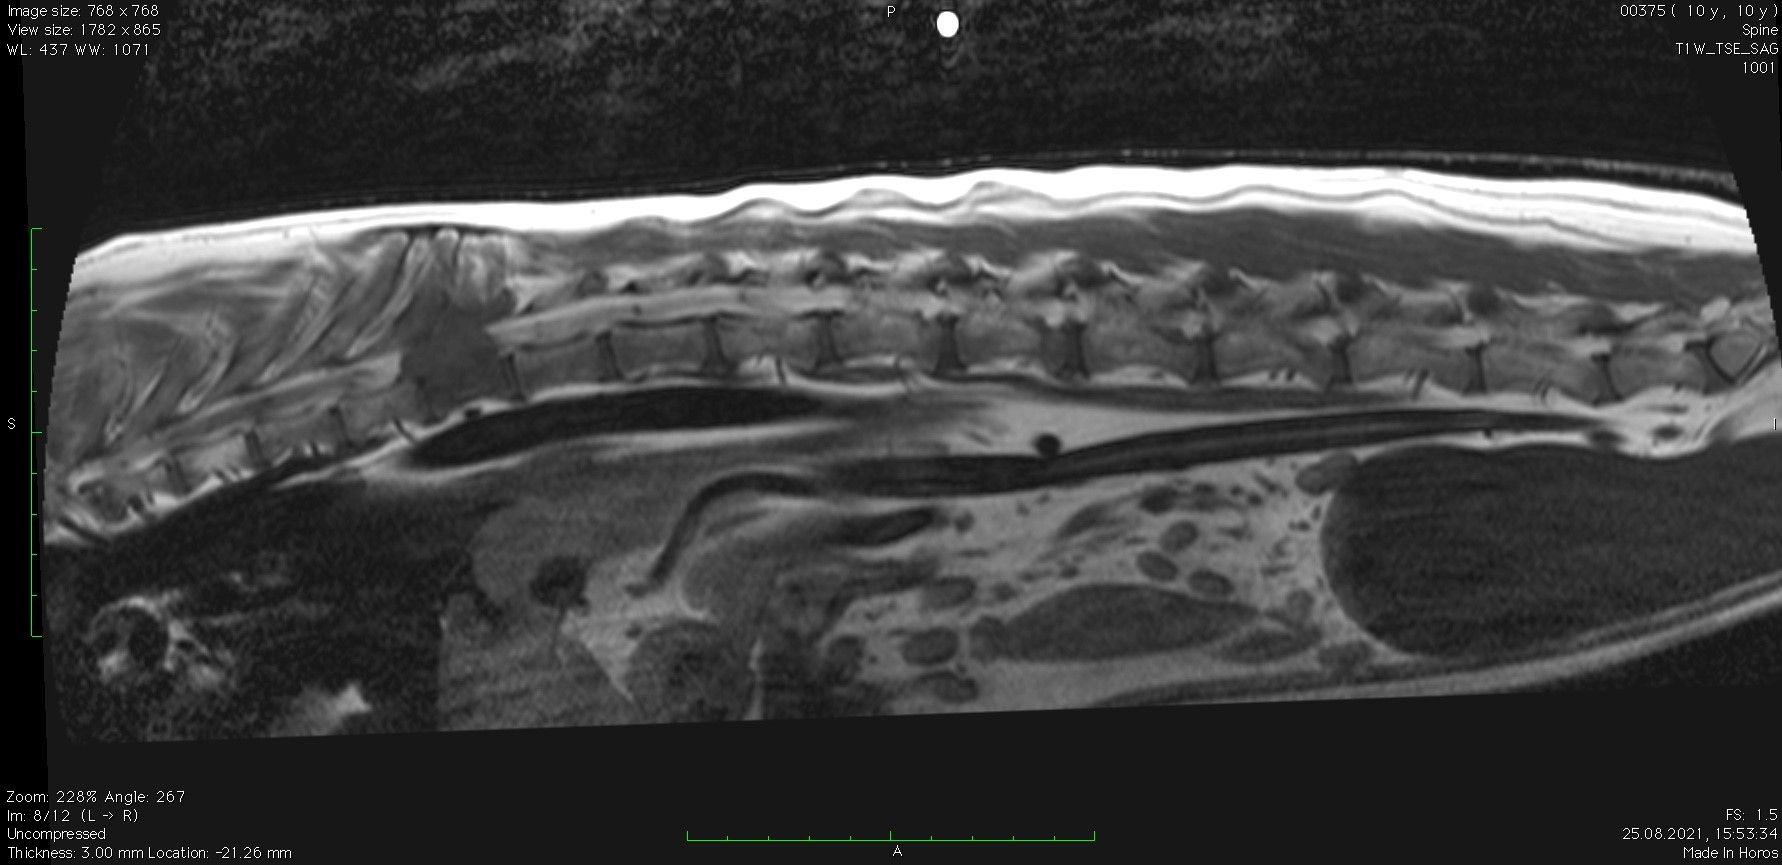

Заключение МРТ:

Признаки очагового образования с накоплением контраста в СМК на уровне Th10 (правая сторона) размером 2,2 х 2,3 см с поражением позвонка, окружающие ткани, выраженной компрессией СМ. С левой стороны на данном уровне отмечается артефакты. На уровне Th12-L2, L6-S1 отмечаются протрузии дисков.